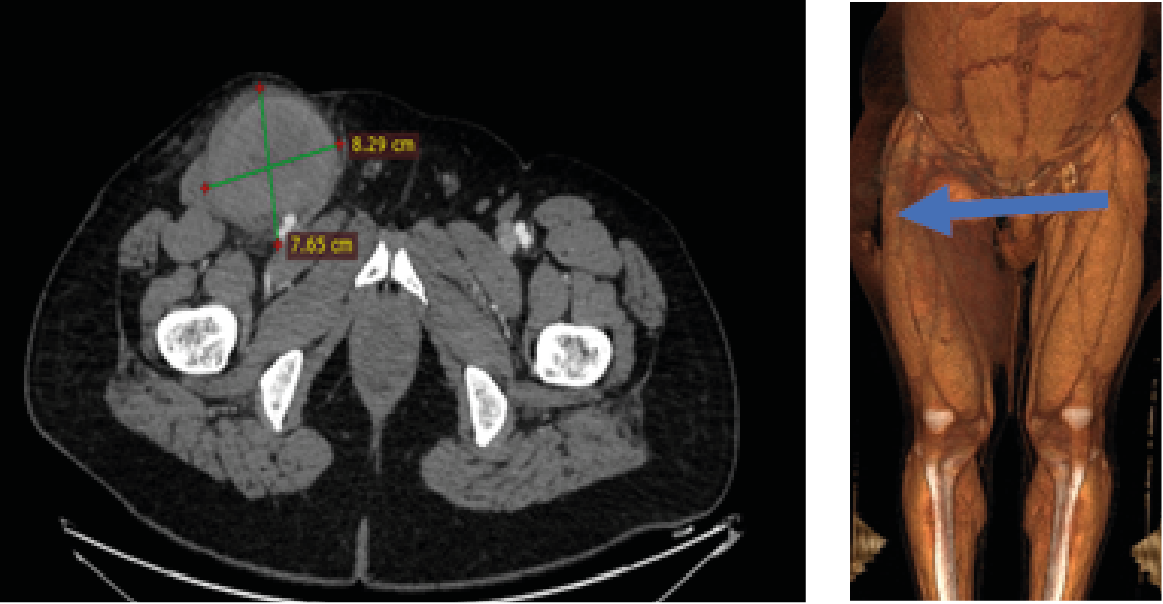

A 42-year-old male who underwent angiography with no obstructive disease found. he was discharged home on the same day but returned to the hospital for Symptoms in- clude groin swelling, unusual pain, bruising, skin changes, neuropathy from femoral nerve compression and claudica- tion from embolization or arterial compression. On examina- tion pulsatile mass in his right groin with a bruit. Angio CT suggested large pseudoaneurysm 7x8 cm in right femoral artery [figure1]. Angiography to his right common femoral artery revealed large pseudoaneurysm [2]. With a contra- lateral sheath placed in the left common femoral artery, the pseudoaneurysm was entered through the neck using 0.014 inch coronary wire. A micro introducer needle was then used to enter the pseudoaneurysm A 0.014-inch wire was then ad- vanced through the neck of the pseudoaneurysm retrograde- ly into the external iliac artery. The micro introducer sheath was then advanced into the pseudoaneurysm over the wire and retrogradely into the external iliac artery. The 0.014-inch wire was exchanged with a 0.035-inch Whole wire. The star closure device was then deployed with the anchor against the pseudoaneurysm neck with subsequent thrombosis of the pseudoaneurysm [figure 3]. Control Angiography through the contralateral sheath showed complete occlusion of the neck with no compromise to the common femoral artery.

Figure 1: CT angiography: large pseudoaneurysm in right femoral artery